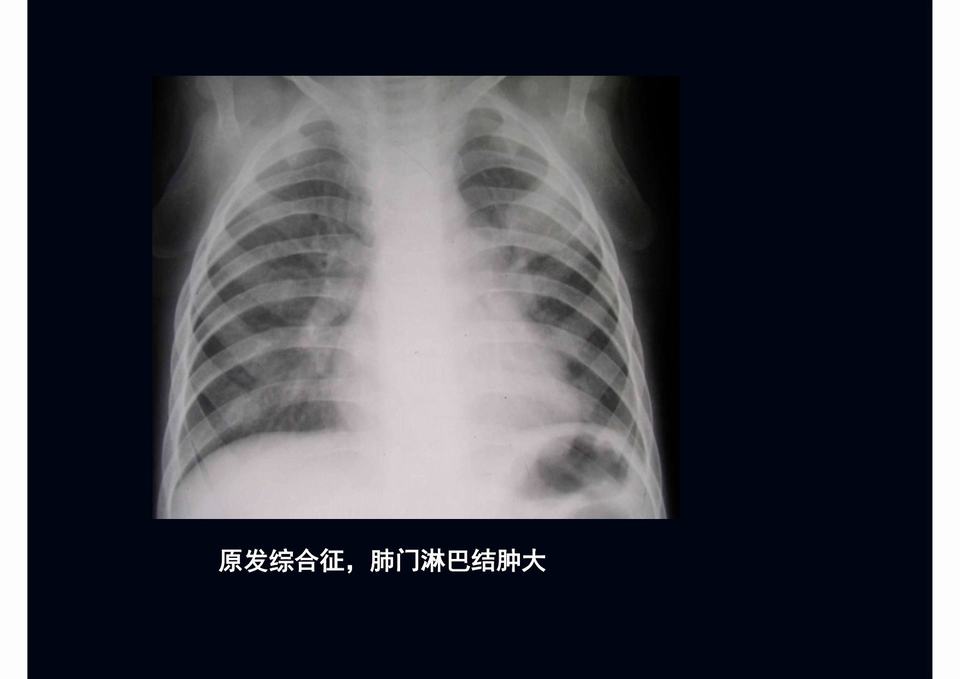

图03